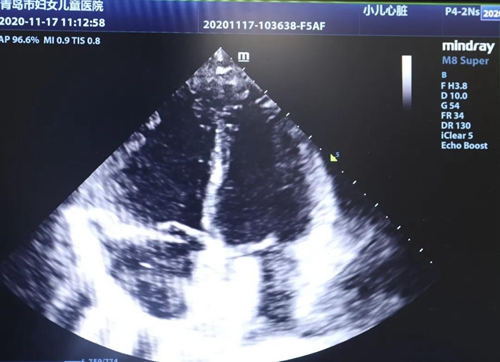

8歲女孩依依(化名)診斷為“先天性房間隔缺損”,合并有“嚴(yán)重的脊柱側(cè)彎”,曾先后于北京接受5次脊柱矯治手術(shù)并在椎骨植入鈦合金矯正支架。1年前依依曾于外院接受房間隔缺損介入封堵治療,遺憾的是手術(shù)未能成功。因此,入院后醫(yī)護(hù)人員為依依進(jìn)行了詳細(xì)檢查評(píng)估。依依的胸部CT檢查提示左側(cè)肋骨缺如伴胸廓畸形,外科開胸手術(shù)修補(bǔ)房缺創(chuàng)傷大,可能影響胸廓修復(fù)。心臟中心團(tuán)隊(duì)仔細(xì)評(píng)估房缺位置及形態(tài)后,符合介入封堵手術(shù)條件,依然決定實(shí)施房缺介入封堵治療。因依依脊椎植入鈦合金支架,常規(guī)透視下經(jīng)導(dǎo)管介入治療手術(shù)視野遮擋,心臟中心團(tuán)隊(duì)為孩子實(shí)施單純經(jīng)胸超聲引導(dǎo)下房間隔缺損封堵術(shù),手術(shù)順利完成。